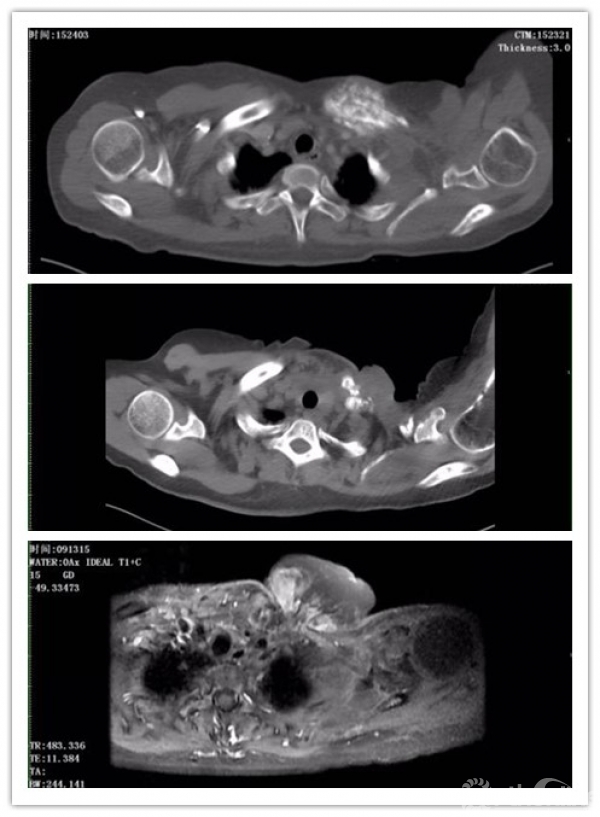

影像学图片:图a,20160919左侧锁骨切除前 胸部CT;图b,20170208左侧锁骨区穿刺前胸部CT;图c,20170318全身化疗2周期后胸部MRI

患者及家属拒绝再次化疗,予内分泌治疗(法乐通+诺雷德)和唑来磷酸抗骨转移。2016年2月29日因自觉左锁骨疼痛较前进行性加重就诊湖北省肿瘤医院,胸部CT平扫增强示“左乳癌”术后改变,较前无明显变化;左侧锁骨胸骨端病灶较前无明显变化。2016年3月8日在全麻下行左锁骨骨肿瘤切开活检术,术后病检示骨软骨瘤。2016年10月19日在全麻下行左锁骨切除术,术后病理示骨增生性改变,结合病史考虑放疗后骨增生改变。

2017年1月27日发现左锁骨区肿物,约豌豆大小,后肿物逐渐增大。2017年2月7日在彩超下行胸壁肿物穿刺活检,病理诊断:(胸壁肿物穿刺活检)恶性肿瘤,结合免疫组化及原锁骨切除病史,考虑为骨肉瘤。

IHC示:肿瘤细胞GATA3(-)SATB2(+) Vim(+) PCK(-) ER(-) PR(-) HER-2(-) KI-67(Li:60%)。2017年2月8日锁骨上区MRI示:1、“乳癌”术后、“左锁骨切除”术后改变,左侧术区肿块,考虑肿瘤复发,累及甲状腺左侧叶、胸骨及上纵隔;2、上段胸椎结节影,较前稍增大;3、右侧锁骨上区多发小淋巴结肿。于20170217以“IFO3.0D1-5ivgtt”方案化疗1周期,于20170316开始以“DDP40mgD1-3”方案化疗1周期,并予抑酸、止吐、保肝及对症支持治疗。